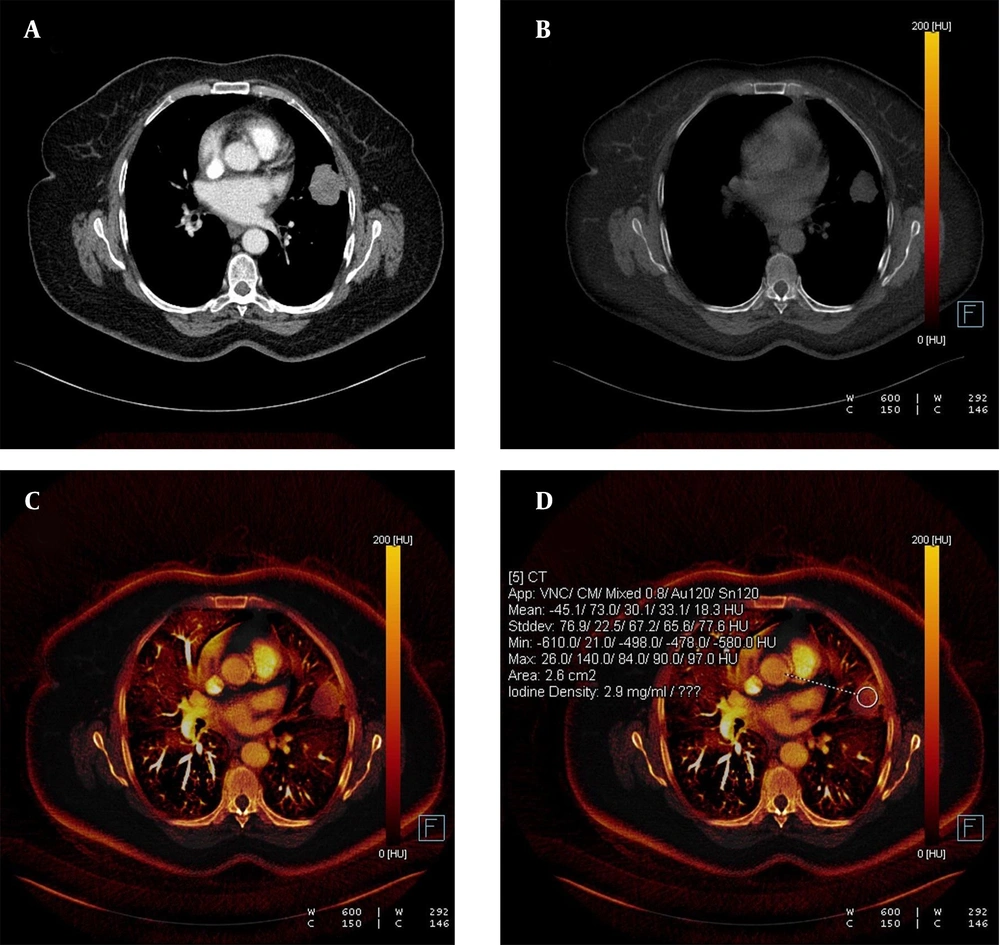

Each nodule was evaluated by a radiologist with 14 years of experience in thoracic imaging who was blinded to the histopathological results and previous radiologic features of the patients. To minimize bias in image analysis, a second radiologist was consulted in cases of disagreement, and if necessary, a third experienced radiologist provided the final decision. The first evaluation involved a qualitative visual assessment, in which a VNC image of the iodine component in translucent mode was displayed as a background color overlay. The manufacturer-defined iodine retention value was set at higher than 50% for default color-coding. The presence of any color (orange or red) in the nodule was considered indicative of contrast enhancement, while a black color (no color-coding) was interpreted as the absence of contrast enhancement. The results were recorded in a binary format as "present" (orange-red) or "absent" (black) (Figures 1 and 2).

A, The weighted average image; B, The virtual non-enhanced image; C, The iodine-enhanced image; and D, The image of the iodine load are observed in dual-energy computed tomography, DECT. C - D, The iodine component is shown as a color overlay on a background virtual non-enhanced image in translucent mode.